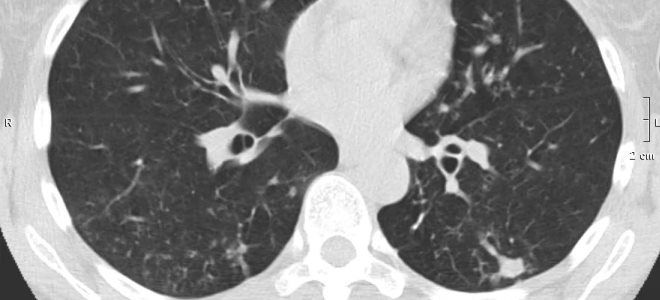

Компьютерная томография (КТ) и магнитно-резонансная томография (МРТ) также могут быть использованы для более детального изучения анатомии почек и окружающих тканей. Эти методы позволяют получить послойные изображения и оценить состояние сосудов, что может быть важно для планирования хирургического вмешательства в случае необходимости.